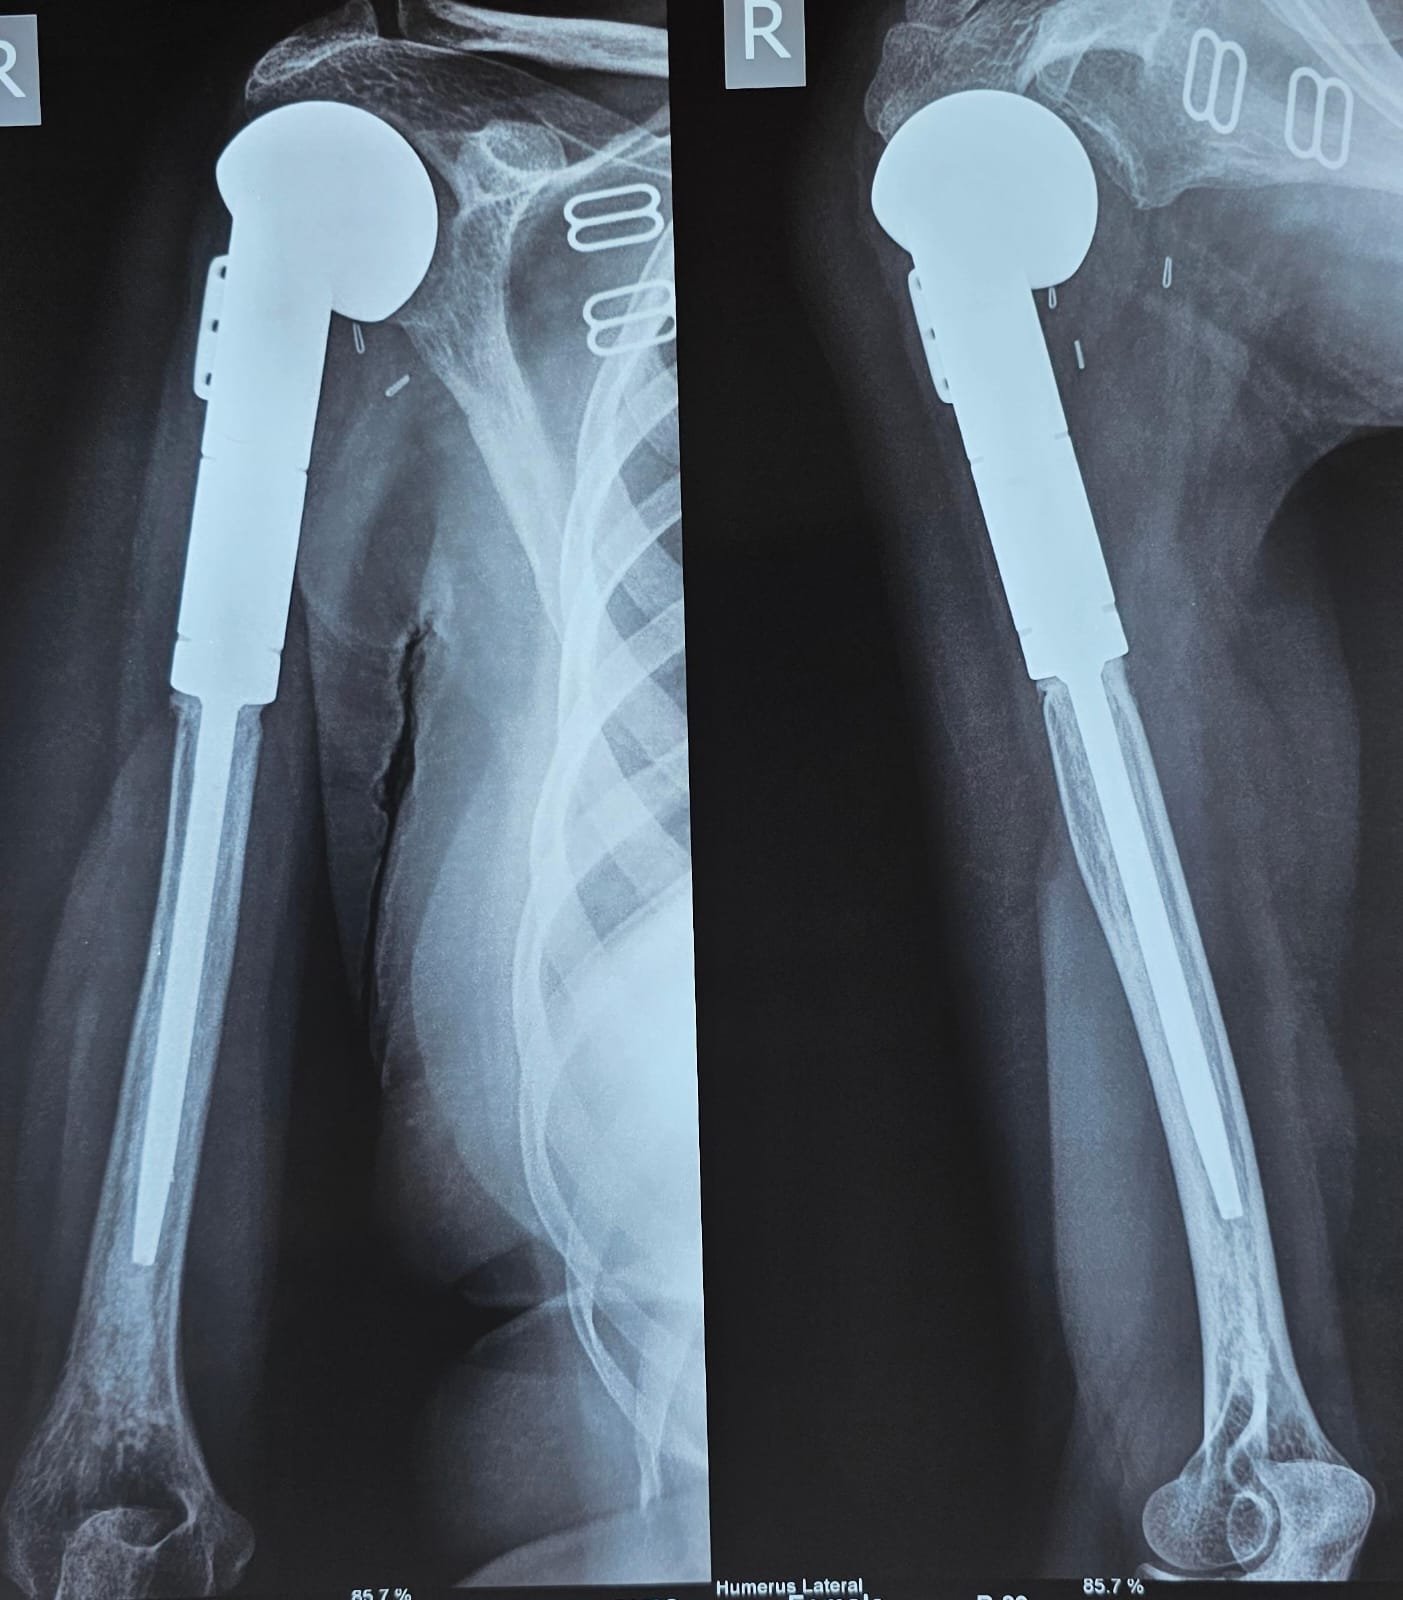

Sarcoma of Humerus

2 of my young kids - one from Uzbekistan and the other one from Kyrgidran. Both suffering from sarcoma of humerus. Now planning to go back to their country after a successful limb saving surgery.

Total Humerus Replacement

A rare surgery to achieve limb salvage surgery. This involves replacement of shoulder and elbow joint along with total humerus body.